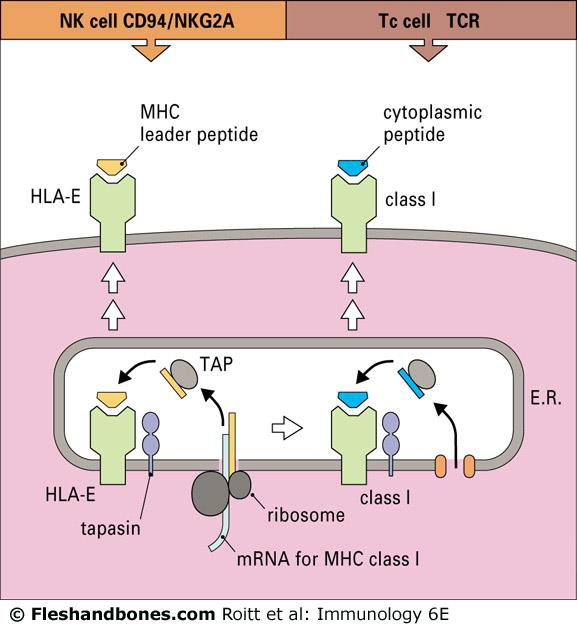

MHC I (內源性抗原呈現)

- MHC I α chain 在ER 製造,calnexin 幫助組裝

- MHC I α:β2 形成, calnexin 放手

- calreticulin, ERp57不讓MCH結合

- Tapsin 幫助結合 TAP (transporter associated with antigen processing)

- Proteasome 打爛 protein,餵給 MHC,TAP 審查肽鍊長度(8-16 → 8-10)

- 運輸到細胞膜

- TCR 和 α3 結合

MHC II (外源性抗原呈現)

- protein 先被 endosome/lysosome 打爛

- Li 在 ER 卡著 MHC

- 丟出 endosome,和 lysosome 結合

- 酸性下LIP10水解,CLIP 繼續卡

- HLA-DM 解開 CLIP

- TCR 結合 β2

- Li

- 恆定鏈, invariant chain,CD74

NK cell inhibitory receptor

- CD94 認 HLA-E

- HLA E

- human leukocyte antigen E,一種 MHC I ,一般的MHC I 呈現抗原,HLA E 呈現製造 MHC I 剩下的垃圾。